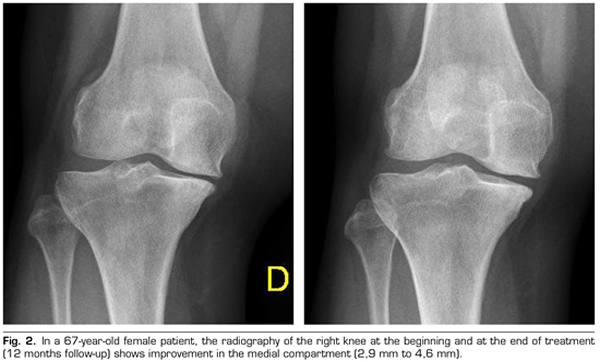

Regarding the radiological variables, when evaluating 53 out of the 115 patients who completed one year of follow-up after ozone treatment, it was observed that the internal compartment increased significantly by 4.12 ± 1.41 mm to 4.4 ± 1.35 mm (p = 0.0008) and the external compartment increased from 6 ± 1.37 to 6.16 ± 1.4 mm (p = 0.0753) (Table II). Two clinical cases are presented as a sample of the radiological change in the internal and external compartments (Figures 2 and 3).

After a year of follow-up with radiological controls on 53 out of the 115 patients in the study, ozone (O2-O3) has been able to increase the minimum joint space of the medial compartment (from 4.12 to 4.44 mm) and the lateral compartment (from 6.0 to 6.16 mm), reversing knee osteoarthritis in our case series. This finding suggests the disease modifying effect of ozone (O2-O3) on knee osteoarthritis, findings that is consistent with the recently reported by Fernández-Cuadros et al. (9).